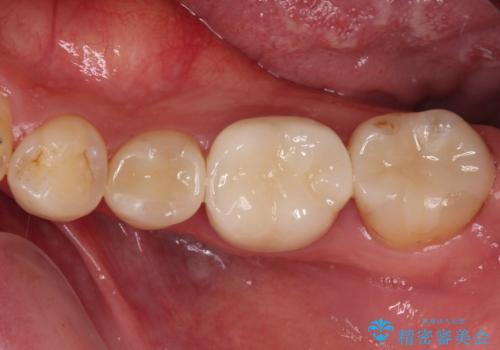

奥歯には目立つ銀歯が多くあるので、矯正治療後には下顎の銀歯をセラミッククラウンやセラミックインレーにより、補綴・修復治療することとしました。

上顎歯列全体を後方に移動させたため、口元の突出感も改善され、装置を外してからは口が閉じやすくなりました。

また、上下犬歯が接触するようになったため、奥歯にストレスのかからない歯ぎしりができるようになり、顎の疲れも改善されました。